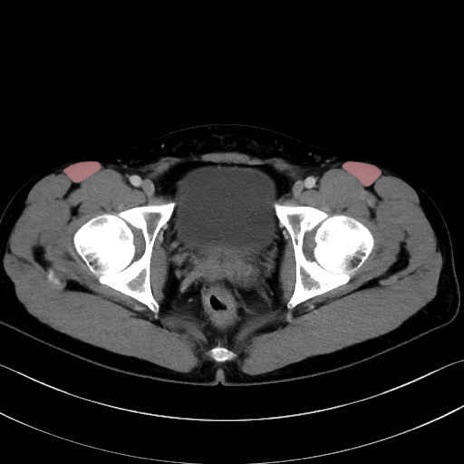

3. 殿部の筋肉(表層・中層・深層)

大殿筋 (Gluteus maximus)

中殿筋 (Gluteus medius)

小殿筋 (Gluteus minimus)

大腿筋膜張筋 (Tensor fasciae latae)